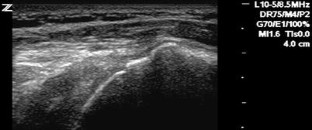

Bildgebende Verfahren bei Rotatorenmanschettendefekten der Schulter

Imaging in evaluating rotator cuff tears

Vor der Indikation zur bildgebenden Diagnostik steht die klinisch begründete Verdachtsdiagnose. Die Basis der bildgebenden Diagnostik bei Rotatorenmanschettendefekten bilden die konventionelle Röntgendiagnostik und die Sonographie. Für spezielle Fragestellungen bietet sich die Kernspintomographie an. Sehnentotaldefekte können sowohl im MRT als auch mit der Sonographie mit großer Sicherheit erkannt werden. Die Diagnostik von Partialdefekten der Manschette ist weiterhin verbesserungswürdig. Die Sicherheit des nativen MRT in der Diagnostik von Partialdefekten kann sowohl durch die indirekte als auch die direkte MR-Arthrographie deutlich gesteigert werden. Nur die Sonographie bietet bislang die Möglichkeit, im Echtzeitverfahren am bewegten Gelenk zu untersuchen. Mit der dynamischen Muskelsonographie sind zusätzliche Möglichkeiten gegeben, die Funktionsfähigkeit der Muskulatur zu erfassen. Der Einsatz der MRT als Screeningmethode sollte unterbleiben, da mit ihrer Hilfe keine therapeutisch relevanten Informationen gewonnen werden.

Diagnostic imaging in a patient with shoulder pain should be used only after a comprehensive clinical evaluation of the shoulder. X-ray and ultrasonography are the basic diagnostic tools; computed tomography and magnetic resonance imaging (MRI) should be used only with certain indications. Ultrasonography and MRI have comparable accuracy for identifying and measuring full-thickness rotator cuff tears, but the accuracy for identifying partial-thickness still needs to be improved. MR arthrography has significantly improved sensitivity and specificity for partial-thickness tears of the cuff. Only ultrasound provides a real-time examination tool during shoulder movements. Moreover, dynamic ultrasonography can assess the contraction patterns of the supraspinatus and infraspinatus muscles, which may improve decision making in the treatment of shoulder diseases. In depicting fatty atrophy of the supraspinatus and infraspinatus muscles, MRI remains the reference standard. MRI should not be used as a diagnostic screening tool in patients with chronic shoulder pain because it does not appear to significantly affect treatment or outcome.